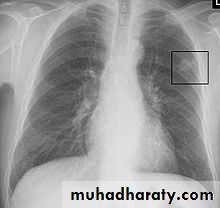

• Differential diagnosis of a solitary lung lesion (COIN LESION)

• 1-Hydatid cyst 4- Primary benign lesion• 2-Tuberculoma 5-primary malignancy of the lung

• 3-Angiomatous malformation (AV fistula) 6-metastatic tumors

• A-Asymptomatic• Any smooth homogenous opacity of uniform density with clear cut border and little or no reaction around it on a chest X-Ray is a hydatid cyst unless proved the other wise .